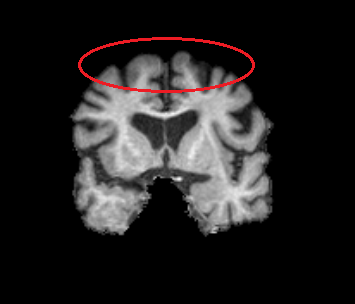

I am running 5ttgen fsl using a brain-extracted T1 image that shows relatively low contrast in the circled area:

I used 5ttgen fsl T1_brain.nii.gz 5TT.nii.gz -premasked -nocrop